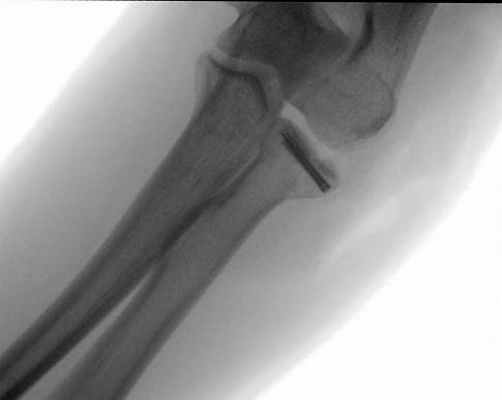

Пациентка И., 39 лет, получила травму локтевого сустава, катаясь на роликах, упав на вытянутую руку. Самостоятельно обратилась в приемное отделение городской больницы 40. При поступлении выполнено рентгенологическое обследование (рис. 1).

Выполнена гипсовая иммобилизация в функциональном положении. Для уточнения диагноза и предоперационного планирования пациентке выполнено КТ-исследование (рис. 2).